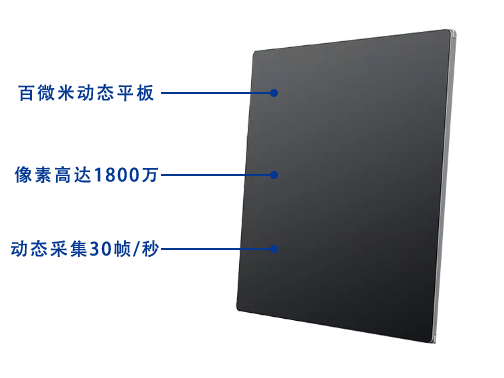

搭載17x17英寸動態平板探測器,動態幀率高達30幀/秒,突破傳統盲拍局限,通過動態實時連續成像,對于重疊部位、易被遮擋的病灶進行多角度動態觀察,瞬時實現高清點片,提升篩查診斷的精準性。